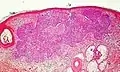

Basal-cell carcinoma with nodular pattern.

Nodular basal-cell carcinoma (also known as "classic basal-cell carcinoma") accounts for between 50% and 80% of all BCC.[2] It most commonly occurs on the sun-exposed areas of the head and neck.[2] Histopathology shows aggregates of basaloid cells with well-defined borders, showing a peripheral palisading of cells and one or more typical clefts.[17] Such clefts are caused by shrinkage of mucin during tissue fixation and staining.[18] Central necrosis with eosinophilic, granular features may be also present, as well as mucin. The heavy aggregates of mucin determine a cystic structure. Calcification may be also present, especially in long-standing lesions.[17] Mitotic activity is usually not so evident, but a high mitotic rate may be present in more aggressive lesions.[17] Adenoidal BCC can be classified as a variant of NBCC, characterized by basaloid cells with a reticulated configuration extending into the dermis.[17]